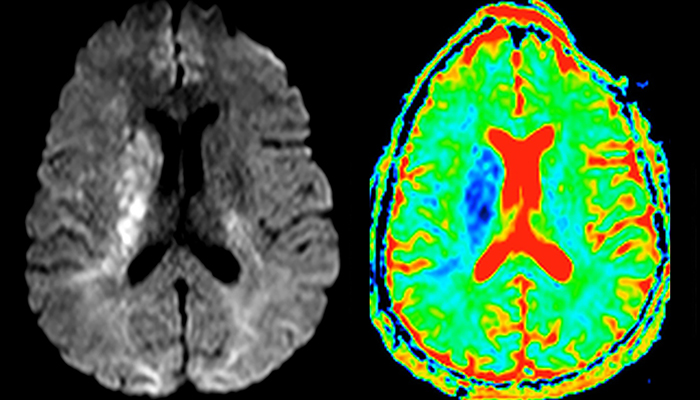

“In France, every stroke is usually imaged with MRI, not CT, even for emergency treatment.” “In France, stroke is usually imaged with MRI, not CT, even for emergency treatment. This is because MRI helps us directly visualize ischemia in the acute phase, but can also help rule out differentials such as MS and hematoma. In addition, we can assess the intracranial and extracranial vessels during the same examination,” says Dr. Savatovsky.

The first challenge in MRI of stroke is speed. The patient typically arrives from an ambulance in the MRI preparation room and the installation is done on a separate dock outside the scanner room. “The venous access is placed during the neurological examination. If the delay from the first symptoms allows the patient to receive thrombolysis we do a very fast examination that typically lasts about 11 minutes including the pre-scans. In the case of transient ischemic stroke we usually add ASL perfusion because in some symptoms with negative diffusion, ASL sometimes indicates a vascular origin.”

“Ingenia provides great flexibility in the parameters setting. We can tune a sequence the way we want,” says Dr. Savatovsky. “For example, in a stroke exam we use a FLAIR sequence of about two minutes instead of the four-minute FLAIR we use for MS. The diffusion is 30 seconds, the T2*-weighted scan is 30 seconds, the angiography scan time is less than one minute. Ingenia is a great scanner in that situation; even with these fast sequences we can achieve good images with good SNR. When the first sequence tells us that it’s not an ischemic stroke but a hemorrhagic stroke, we may switch to a time-resolved angiography to look for vascular malformations and venous thrombosis.

“Every center is different, but for me the ideal protocol for stroke includes diffusion weighted imaging, FLAIR, and fast susceptibility imaging,” says Dr. Savatovsky. “Our fast susceptibility weighted imaging takes 50 seconds, so it’s as fast as T2*-weighted imaging. It visualizes hemorrhage but also the clots. We also do 3D MR angiography that provides information on cervical and brain vessels. If the patient does not need immediate treatment, or if additional information is needed to decide on treatment, we might also add perfusion imaging and post-contrast T1-weighted imaging.”